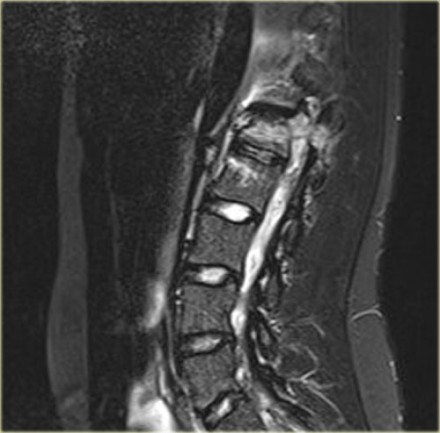

Scroll through the images.

What are the findings?

The findings are:

- The main feature is posterior distraction with horizontal fractures of posterior elements (red arrow)

- Avulsion of a spinous process (yellow arrow)

- Widening of facet joint (green arrow)

- Burst-type fracture

In this case some would call this a burst fracture with PLC-injury i.e. 2+3 points.

However the distraction is the most important finding, i.e. distraction and PLC injury, i.e. 4+3 points.

Continue with the MR.

The MRI shows exactly the same things.

Frequently when you have a good CT, you have most of the anatomic information.

The MRI also shows disruption of the ligamentum flavum and a partial disruption of the interspinous ligament.

TLICS score:

- Morphology: distraction - 4 points

- PLC injury - 3 points

This patient is at high risk of developing a spinal cord injury.